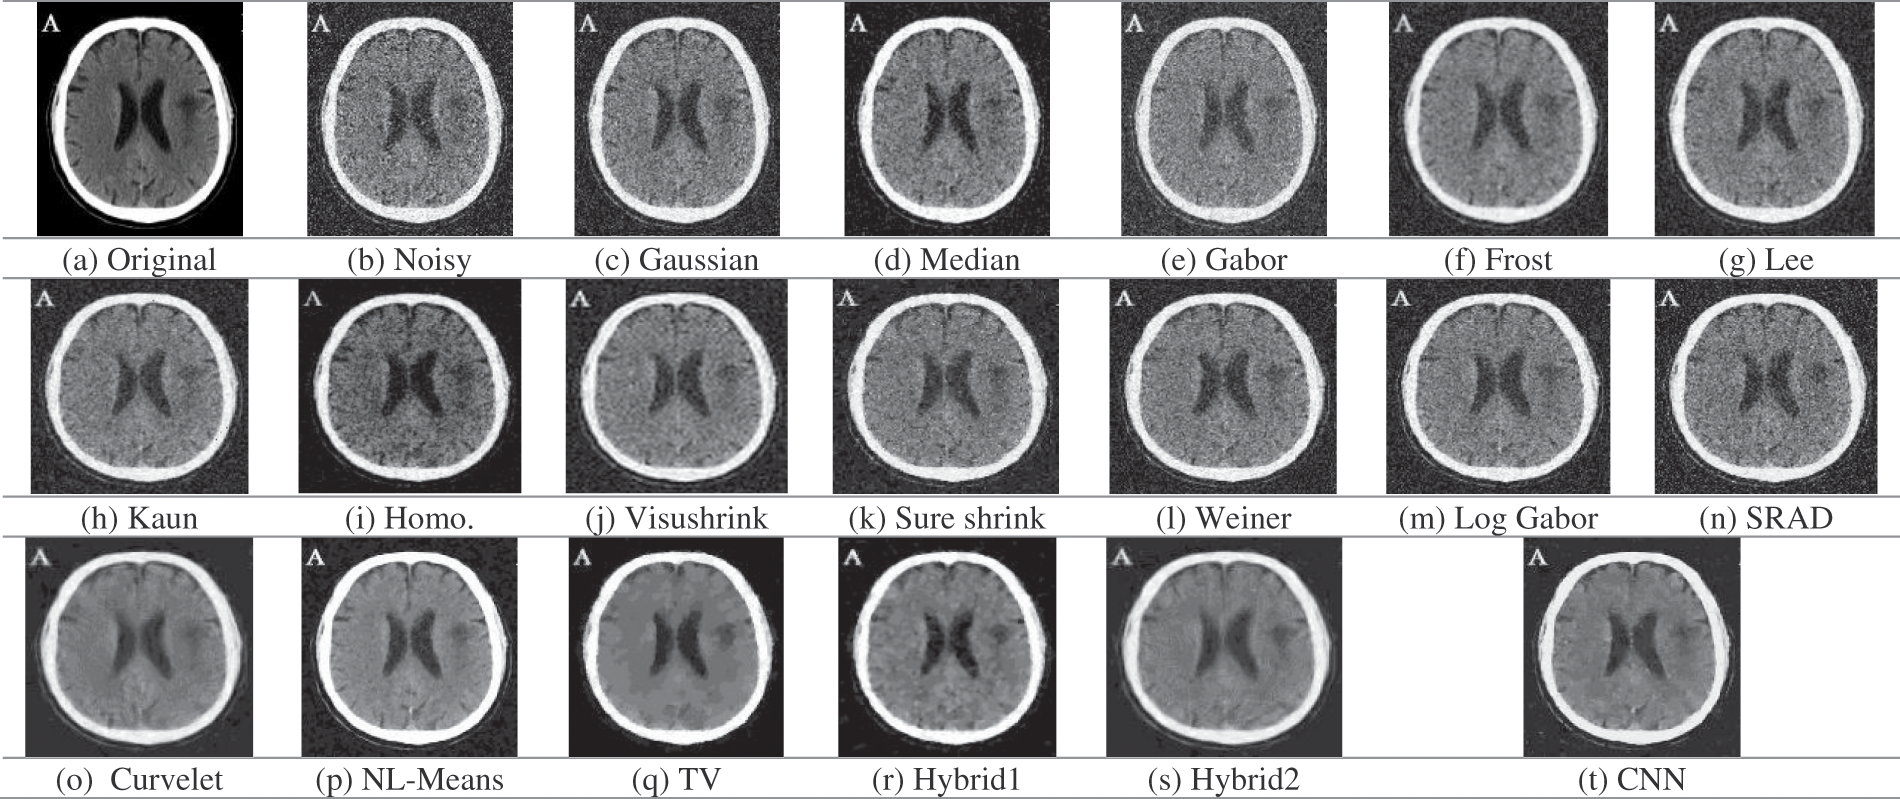

Figure 5: Obtained outcomes for the examined denoising filters for the CT image at 0.05 gaussian variance

Fig. 5 shows the original, noisy, and output denoising results of the CT brain images. The traditional denoising techniques, including Gaussian, median, Gabor, Lee, Kuan, homomorphic, wavelet-based, Log-Gabor, and SRAD techniques, poorly represented texture details, and poorly removed the Gaussian noise. On the other hand, the NL-Means filter and the denoising CNN model preserve edges and preserve texture details compared to the other techniques. Tab. 3 shows the Cr and PSNR values for noisy and denoised images. We have found that the TV and hybrid1 techniques have the best PSNR output values. Indeed, they have the highest value of PSNR of 24.3905 dB (for TV) and 24.2884 dB (for hybrid 1) compared to 23.7056 dB (for NL-Means) and 22.1856 dB (for the denoising CNN) at 0.05 Gaussian noise variance. Through the presented results, we conclude that the NL-Means and CNN models show the best results and are considered the best models in reducing noise and preserving accurate features in CT brain images.